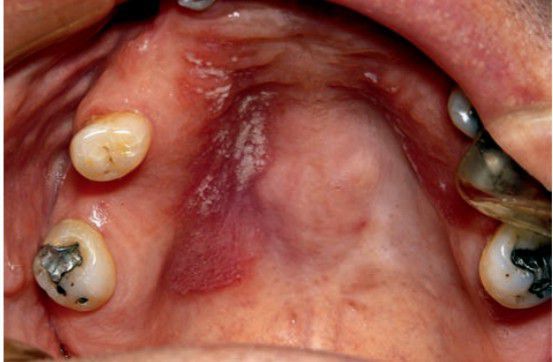

Acute pseudomembranous candidiasis

Acute pseudomembranous candidiasis presents as white soft plaques.